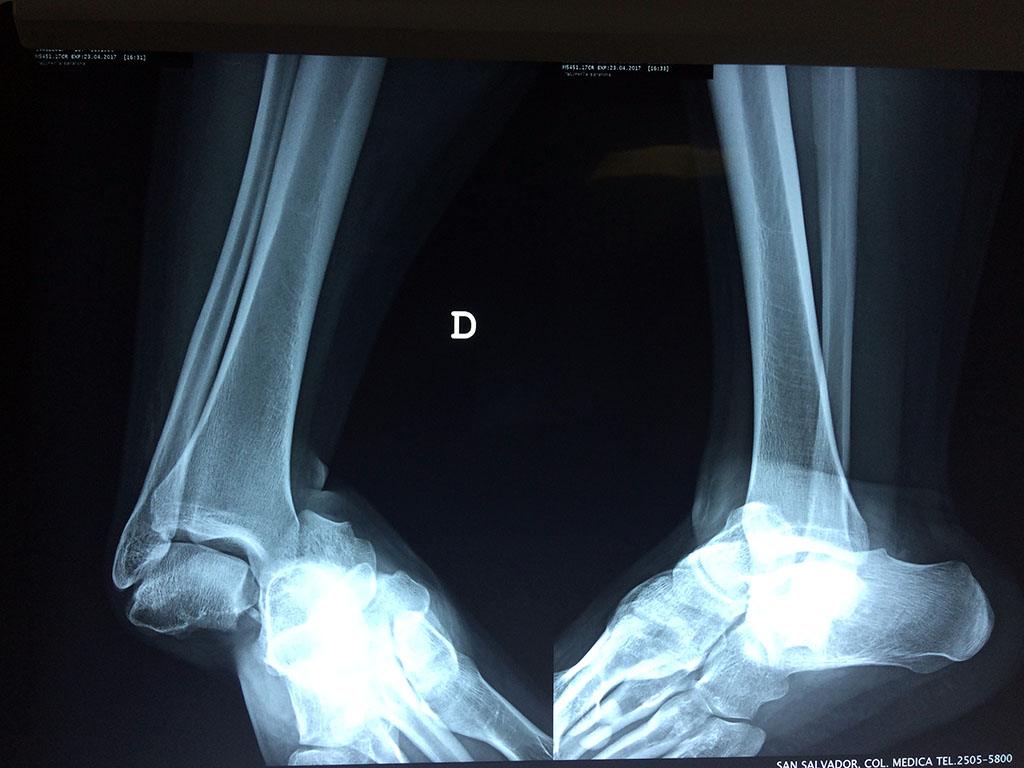

Una fractura de tobillo es la rotura de uno o más de los huesos del tobillo. Estas fracturas pueden ser:

- Parciales (el hueso está sólo parcialmente fisurado, no del todo).

- Completas (el hueso está perforado y está en 2 partes).

- Producirse en uno o ambos lados del tobillo.

Algunas fracturas de tobillo pueden requerir cirugía si:

- Los extremos de los huesos están desalineados entre sí (desplazados).

- La fractura se extiende hasta la articulación del tobillo (fractura intra-articular).

- Los tendones o ligamentos (tejidos que sujetan los músculos y los huesos entre sí) están rotos.

- El médico cree que sus huesos probablemente no sanen apropiadamente sin cirugía.

- El médico considera que la cirugía puede permitirle una recuperación más rápida y confiable.

- En los niños, la fractura involucra la parte del hueso del tobillo donde el hueso está creciendo.

Cuando se necesita cirugía, es probable que esta implique el uso de clavijas de metal, tornillos o placas para sostener los huesos en su lugar mientras la fractura se consolida. Los elementos de soporte pueden ser temporales o permanentes.